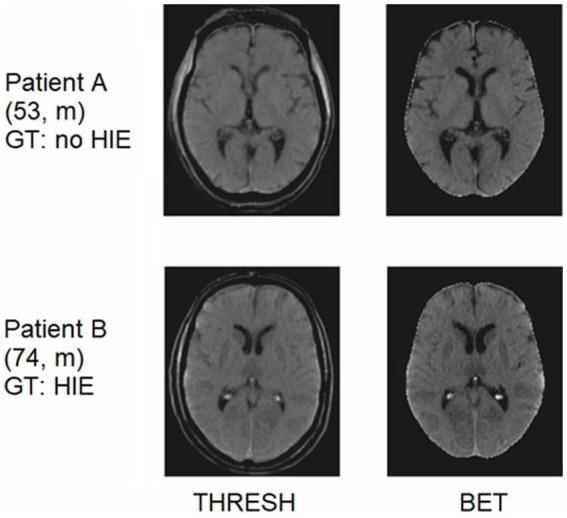

168 head CT scans of patients after cardiac arrest were retrospectively identified and classified into two categories: 88 (52.4%) with radiological evidence of severe HIE and 80 (47.6%) without signs of HIE. These images were randomly divided into a training and a test set, and five deep learning models based on based on Densely Connected Convolutional Networks (DenseNet121) were trained and validated using different image input formats (2D and 3D images).

All optimized stacked 2D and 3D networks could detect signs of HIE. The networks based on the data as 2D image data stacks provided the best results ( AUC: 94%, ACC: 79%, AUC: 93%, ACC: 79%). We provide visual explainability data for the decision making of our AI model using Gradient-weighted Class Activation Mapping.